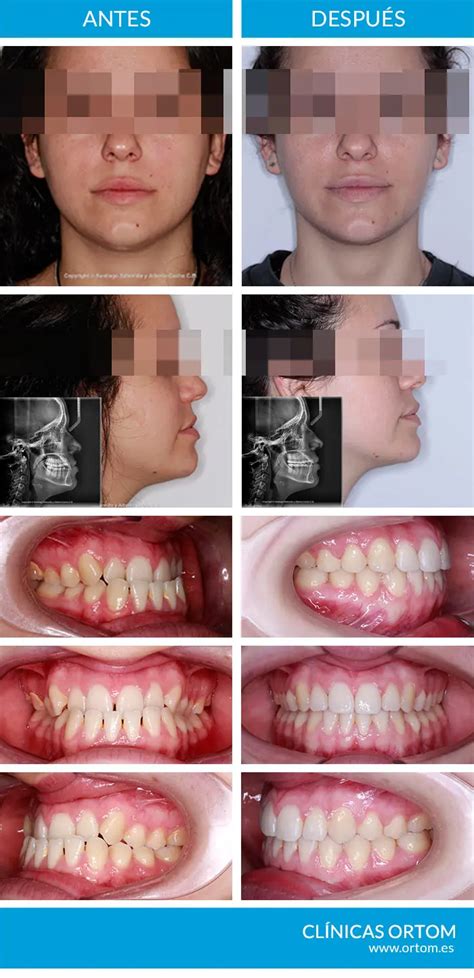

¿Cómo Cambia la Cara con Brackets?

Sí, los brackets (frenillos) pueden producir cambios faciales pero de manera positiva y generalmente sutil. Lo más común es que mejore la armonía facial: tu sonrisa se ensancha, el perfil se equilibra, y la posición de la mandíbula encaja mejor dando un aspecto más estético.

En pacientes jóvenes (niños y adolescentes) los cambios faciales pueden ser más notables que en adultos, porque sus huesos aún están en crecimiento y la ortodoncia puede guiarlos en cierta dirección. En adultos, el hueso ya es más denso y las suturas están cerradas, así que la mayoría de cambios serán por movimiento dental y adaptaciones de tejidos blandos, más sutiles.

Con brackets podemos cerrar la mordida abierta haciendo que los dientes frontales superiores e inferiores entren en contacto adecuado. Esto conlleva un reposicionamiento de la mandíbula y un entrenamiento de los músculos faciales para que los labios puedan cerrarse cómodamente. El antes y después es notable: de un rostro donde los labios no cerraban y se veía alargado, se pasa a un rostro más corto y armonioso.

Con ortodoncia podemos corregir en parte el prognatismo, especialmente si se trata de un problema dental (y no solo óseo). Esto implica llevar los dientes inferiores hacia atrás y/o los superiores hacia adelante hasta que encajen correctamente. Al finalizar, la zona del mentón se ve menos prominente. El perfil deja de ser tan cóncavo para volverse más recto o convexo suave (lo ideal).

Con brackets corregimos la sobremordida elevando los dientes inferiores y/o bajando los superiores hasta que haya una mordida ideal: los incisivos de arriba cubriendo solo ~2mm de los de abajo. El cambio estrella aquí es que el paciente, de tener un mentón poco definido o “metido”, pasa a lucir un perfil más recto, con el mentón más marcado.

No todos los cambios faciales vienen de grandes maloclusiones. Alinear dientes apiñados con brackets mejora la simetría de tu sonrisa y da una impresión facial más equilibrada. Con ortodoncia, movemos dientes protruidos hacia adentro a su posición correcta. El cambio en el perfil es notable: el ángulo entre la base de la nariz y el labio superior se abre y los labios se ven más planos contra la cara.

Un reciente estudio científico publicado en 2024 confirmó que los tratamientos ortodónticos mejoran la estética facial, especialmente en la vista de perfil, notando en promedio una ligera retracción de los labios y una mejor definición del mentón tras la ortodoncia.